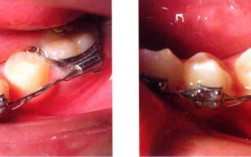

连续结扎的操作需严格遵循无菌原则和轻柔操作理念,避免损伤牙体、牙周及口腔黏膜,以下以非自锁托槽(如方丝弓托槽、直丝弓托槽)为例,详细说明操作流程:

(三)连续结扎操作

- 结扎丝结扎法:

- 取适当长度结扎丝(约10~15cm),用持针器夹住中点,对折后在托槽近中或远中翼下方穿过,使结扎丝两端分别位于托槽颊舌侧。

- 用埃利氏钳夹住一侧结扎丝,另一手固定托槽,将结扎丝顺时针或逆时针缠绕托槽翼2~3圈,确保力度均匀(以能轻微滑动弓丝但无明显晃动为宜)。

- 剪去多余结扎丝,将末端回弯至牙面,避免刺伤黏膜。

- 弹性结扎圈结扎法:

- 用结扎钳夹取弹性结扎圈,张开圈体后套入托槽颊面翼与弓丝之间,缓慢松开钳子,使结扎圈自然回缩包裹托槽翼和弓丝。

- 检查结扎圈是否完全就位,避免部分脱位导致力量不均。